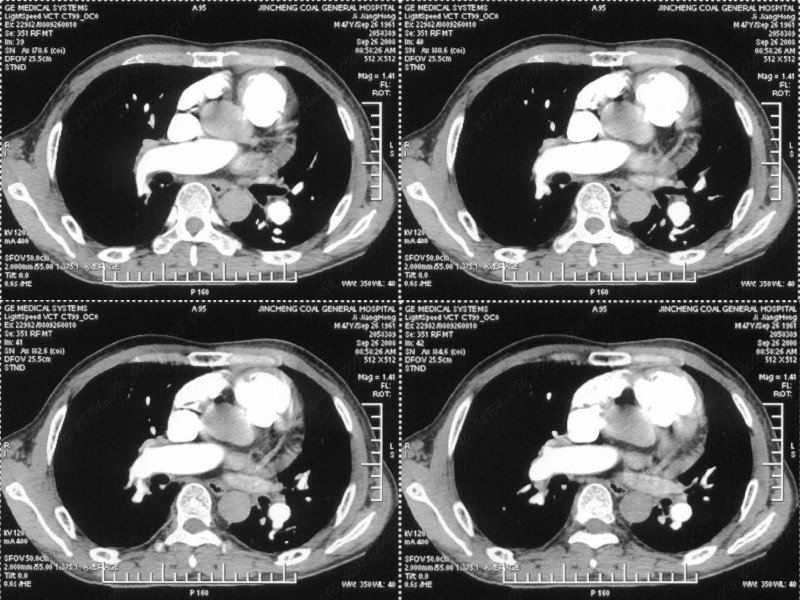

男性,47岁。胸部不适一年,ct检查发现右胸膜下结节。http://www.radida.com/bbs/forum.php?mod=viewthread&tid=46094

图像很清,资料很全。工作做的很细,向您学习!观阁下的强化图像发现,您们强化后扫描时间挺早,延迟时间大约在16—18秒之间吧。估计目的是为了观察肺动脉及分支的情况。但现有的资料并不能提示动脉栓塞改变。建议楼主可在机器上仔细观察,或许会有异常发现。另外,个人感觉右侧应为肺内结节而非胸膜结节。考虑肺内良性小结节,炎性假瘤可能性大。

病灶周围似有纤维化征像,增强明显强化,但中央可见点状低强化区,考虑慢性病变可能如炎性假瘤等,病灶边缘部分毛糙有切迹,双侧胸腔少量积液影,不除外恶性

结节未见明显强化,局部胸膜增后粘连,内缘纹理影增重伴小围星灶,局部胸膜下小三角状实变影,尖端见纤维索牵扯征,综合考虑炎性病变,有增殖表现,不出外tb灶

右肺中叶外侧段胸膜下结节状病灶,性质待定(不排除周围型肺癌可能)。

汇报临床诊断:右肺动脉分枝栓塞

右肺静脉充盈缺损,左心房体积小,右肺动脉远端动脉充盈缺损,右肺血管影细小,考虑;右肺动脉远端栓塞.